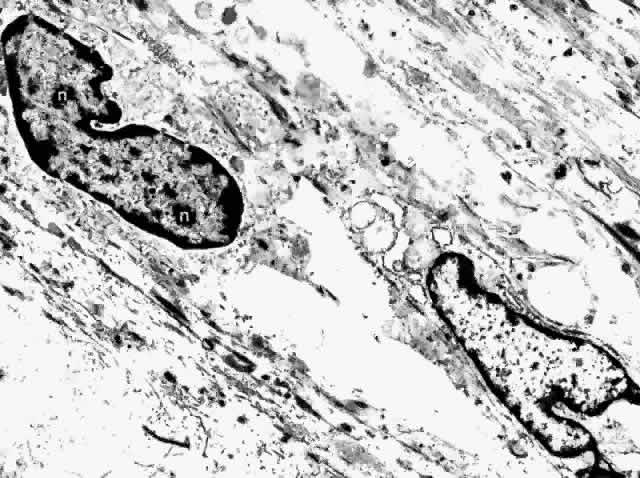

no discernible internal arrangement.63 The fibrocyte is the most common nonpigmented cell found in the choroid (Fig. 31). Its long, spindle-shaped body and processes intermingle with the melanocytes

in the outer choroid, forming syncytia. They are present throughout

the vessel layers and only rarely are seen in the subcapillary

zone of collagen. The cytoplasm of the fibrocyte contains mitochondria, Golgi

apparatus, centrioles, free ribosomes, and rough endoplasmic reticulum.17,22  Fig. 31. Choroidal fibrocytes display nuclei with several nucleoli (n). Extracellular collagen is apparent. (× 9000) Fig. 31. Choroidal fibrocytes display nuclei with several nucleoli (n). Extracellular collagen is apparent. (× 9000)